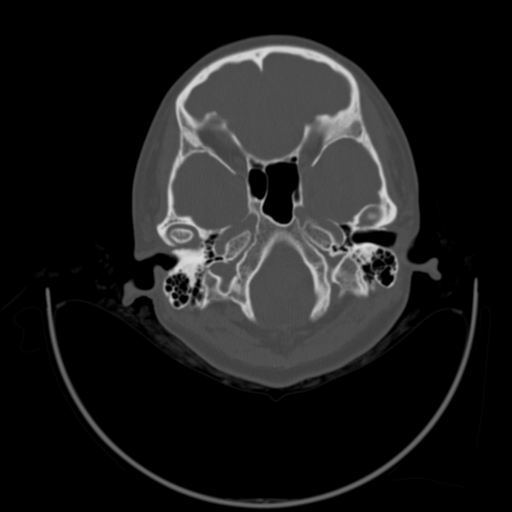

以下是引用随光逐影在2009-3-14 7:58:00的发言:[br]双耳——颞骨ct轴位平扫未见明确异常。